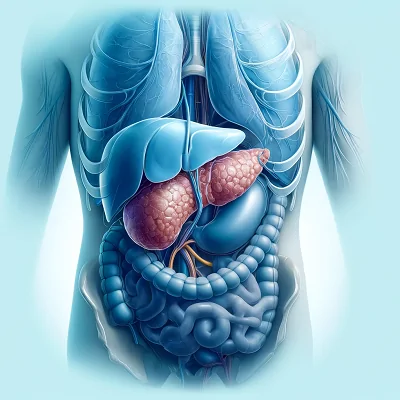

الجراحة التنظيرية

الجراحة التنظيرية هي طريقة جراحية بسيطة يمكن إجراؤها للمعدة أو داخل الحوض، ويتم فيها استخدام المنظار للكشف عن الحالة الطبية أو إجراء العملية، وتعتبر هذه الجراحة أكثر أماناً من الجراحة التقليدية نظراً لأنها أقل تداخلاً جراحياً.

يقوم الجراح بإدخال المنظار من خلال شق جراحي صغير في منطقة البطن بقياس نصف بوصة أو أقل، كما سيقوم الجراح بعمل ما يصل إلى ثلاثة شقوق جراحية أخرى لإدخال أدوات جراحية أخرى حتى يتمكن من مشاهدة جميع الأعضاء في منطقة البطن وتحديد المشاكل الصحية وعلاجها.